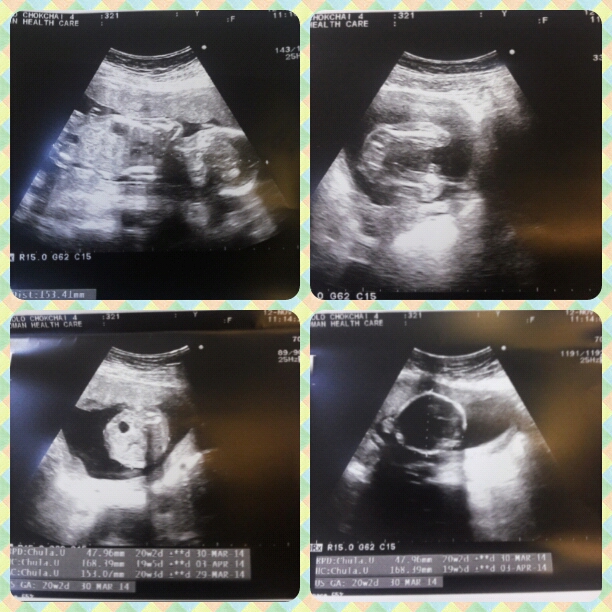

วันนี้ไป u/s ดูเพศมาค่ะ มีเรื่องอยากสอบถาม

วันนี้คุณหมอนัดฝากครรภ์ครั้งที่ 5 เลยขอคุณหมอ u/s ดูเพศ ตื่นเต้นมากๆ ผลออกมาว่า ตรงหว่างขา โล่งเตียนมากค่ะ คุณหมอบอกผู้หญิงแน่นอน

สอบถามคุณหมอถึงน้ำหนักและความยาวของเจ้าตัวเล็ก คุณหมอแจ้งว่า น้ำหนัก 300 กรัม ยาว 15 เซน อยากสอบว่าน้ำหนักและความยาวของตัวเล็กปกติหรือไม่คะ